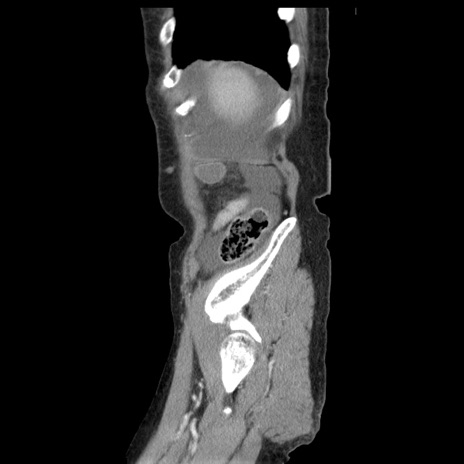

横断像

冠状断像